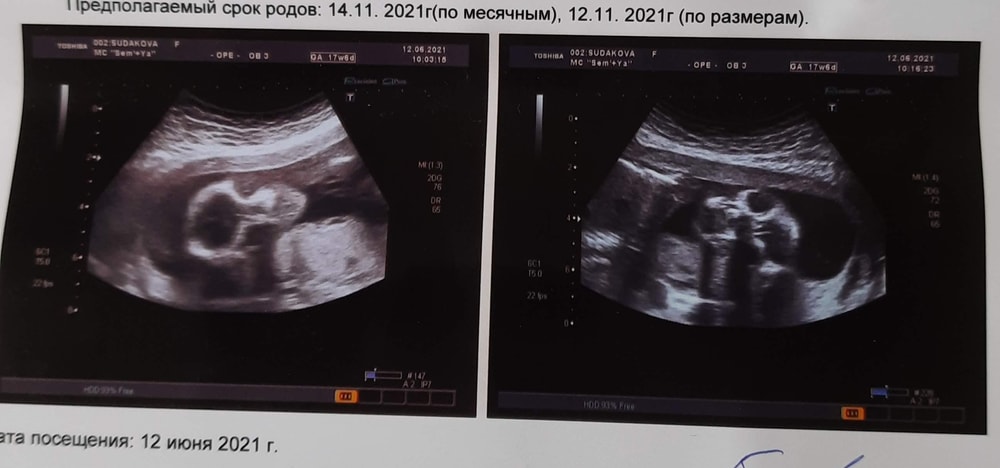

Мне в 3ю Б в 18 недель вот такие фото дали😅

Тоже череп, в анфас🙈